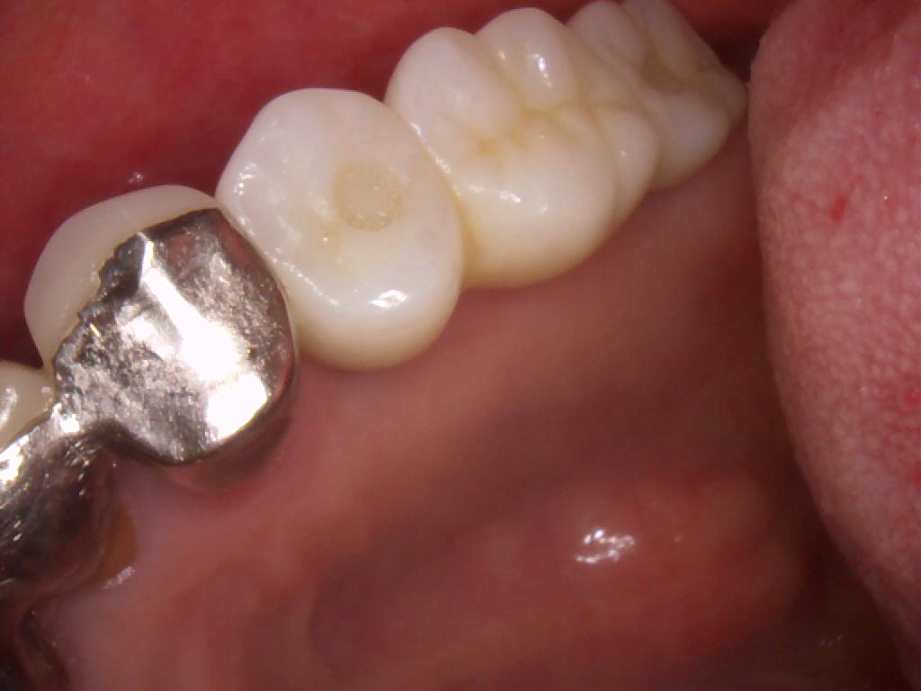

治療後

- 右下6番欠損によるインプラント治療

- 20年前に抜歯してからそのままなのでどうにかしたい。

- まず、CT撮影による精密な骨の分析・治療計画を立てガイドを使いインプラント埋入しインプラントが骨と結合するのを待つ間に仮の歯を入れます。その後本歯を作成して装着しました。

- インプラント埋入からジルコニアセットまで二か月半

※自由診療となります - ■総額¥330,000(税込み) ■内訳:埋入(ガイド込み)¥200,000、仮歯¥20,000、被せ物(ジルコニア)¥80,000